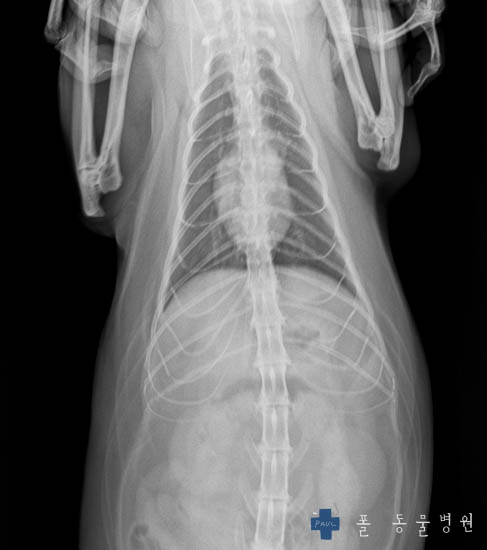

그러면 Xray 촬영을 하게 되는데요.

몸의 골격계, 내부 장기의 형태, 호흡기계 등을 평가하는 중요한 검사입니다.